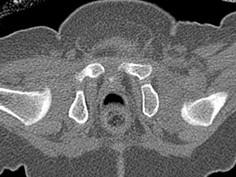

问题 男,3岁,走路跛行,两下肢不等长,左脚外展受限,结合图像,最可能的诊断是 ( )

选项 A、先天性髋内翻 B、髋关节结核 C、髋关节后脱位 D、髋关节中心脱位 E、髋关节前脱位

答案 C